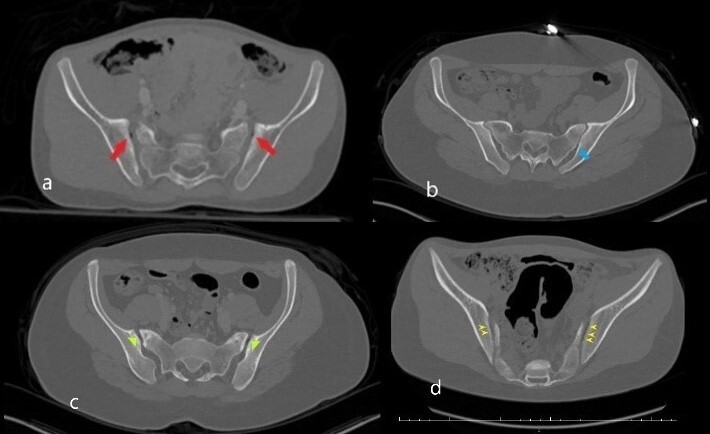

Each study image was assessed by the two blinded radiologists (first author ED and third author SA). Each radiologist independently evaluated the CT images on the coronal, axial and sagittal planes. In case of contradictory results, the images were evaluated together by both radiologists. Imaging evaluations were made at the workstation with a high-resolution medical monitor in soft-tissue window [Windows width (WW): 400 Hounsfield unite (HU), windows level (WL): 50 HU], bone window (WW: 1800 HU, WL: 400 HU) as well as the lung window (WW: 1500 HU, WL: -600 HU) to distinguish air more clearly from soft tissue and bone. The presence of gas (i.e., air) was considered positive for VP in the SIJ (Figure 1).

Patient results were classified according to age groups (0-4 years old, 5-8 years old, 9-11 years old, 12-14 years old, 15-17 years old) as well as gender (male, female). Data according to the presence of SIJ VP were enlisted as right, left and bilateral (Figure 2).

The symmetry and asymmetry of the patterns were examined in patients with bilateral VP. If both sides were in the same patterns, it was accepted as symmetric, while asymmetric in different patterns.9 The patients were divided into VP and non-VP groups for comparison. If gas accumulation in the joint was detected, it was classified in the VP group regardless of whether it was unilateral or bilateral, otherwise, it was classified as non-VP. The related groups were compared according to the appropriate parameters and necessary analyses were completed.